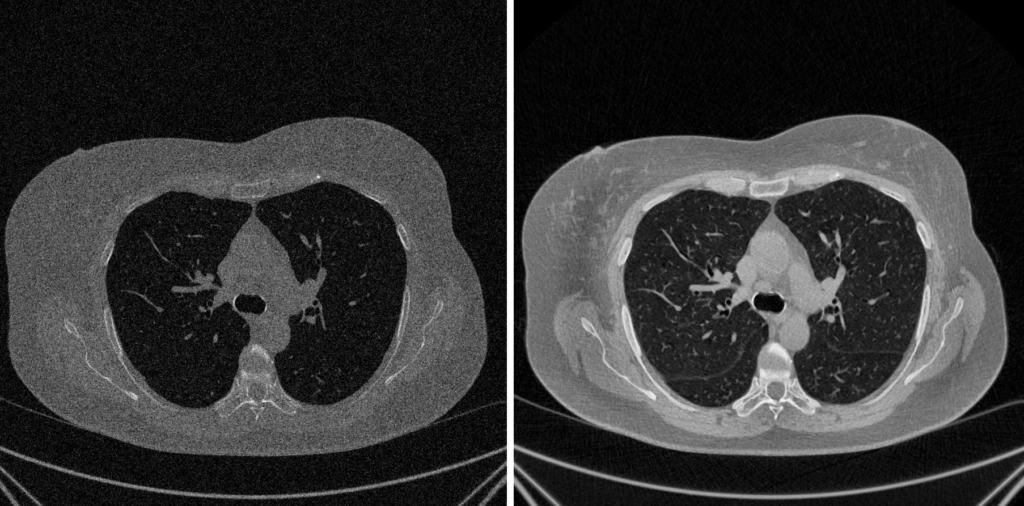

5. Fase 4: Miglioramento Visivo e Contrasto

Un’immagine quantitativamente ineccepibile (ad esempio, un’immagine a 16 bit, CV_16U), dopo le correzioni e i filtraggi, può risultare visivamente “piatta” o troppo scura. Questo fenomeno si verifica quando i dati rilevanti sono concentrati in un intervallo ristretto di livelli di grigio.

E’ allora necessario effettuare un’operazione di “stiramento” dell’istogramma. L’obiettivo è estendere la distribuzione dei pixel per sfruttare appieno la gamma dinamica disponibile sul dispositivo di visualizzazione (ad esempio, da 0 a 255).

Equalizzazione Globale dell’Istogramma (Histogram Equalization – HE)

Questo metodo tradizionale agisce sull’intera immagine per rimappare e ridistribuire le intensità dei pixel in modo uniforme.

- Funzionamento: La tecnica mira a trasformare l’istogramma dell’immagine rendendolo il più uniforme (piatto) possibile. Il principio è che una distribuzione equa di tutti i livelli di grigio massimizza il contrasto complessivo.

- Svantaggi: Essendo un’operazione che considera l’immagine nel suo complesso, aree ampie e poco variegate (come uno sfondo omogeneo) tendono a dominare l’istogramma. Questo può portare a “schiacciare” i dettagli presenti in regioni più piccole e, potenzialmente, ad amplificare notevolmente il rumore di fondo.

Equalizzazione Adattativa dell’Istogramma (CLAHE)

CLAHE rappresenta la soluzione “intelligente” e all’avanguardia per superare i limiti dell’equalizzazione globale, affermandosi come lo standard de-facto nell’imaging medicale.

Principio Fondamentale

A differenza dei metodi che analizzano l’istogramma complessivo, CLAHE opera localmente. Migliora il contrasto solo nelle aree necessarie, evitando al contempo l’amplificazione del rumore di fondo.